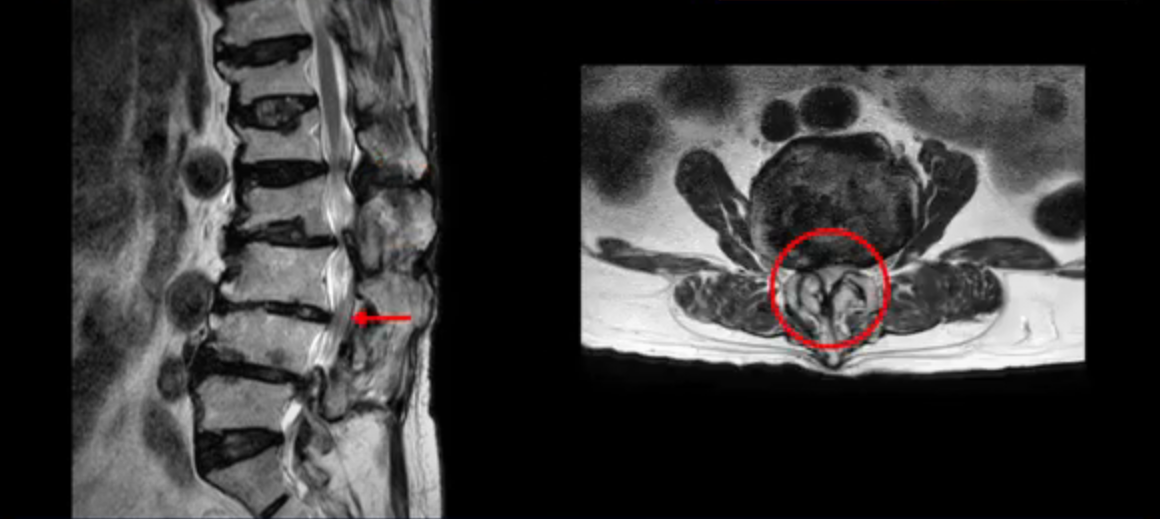

이 환자분은 허리 여러 마디가 다 안 좋아서 오랫동안 허리가 아프셨고 허리도 일찌감치 굽으셨습니다. MRI를 보시면 허리 여러 마디가 심하게 안 좋습니다.

보시다시피 4번 5번 마디에는 심한 중심성 협착이 있고

1번 2번,

2번 3번,

3번 4번에도 중심성 협착이 있습니다.

또 신경 가지가 빠져나가는 추간공도 좁아져 있습니다. 이런 이유로 환자분의 다리가 저리고 아픈 겁니다.

또한 척추뼈 여러 개가 압박 골절과 변형으로 찌그러져 있고

골다공증도 심하시고 보시다시피 근육량이 너무 적습니다. 근육이 정상적인 분들과 비교해보면 근육이 얼마나 적은지 알 수 있습니다.